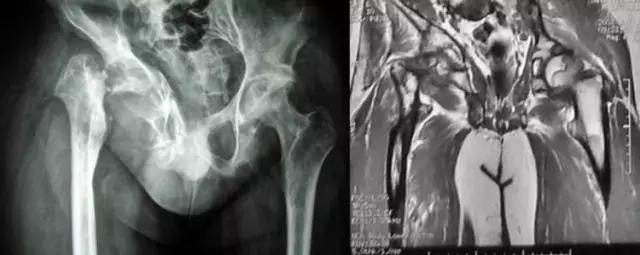

下图是同一个病人的MRI照片,MRI显示的内容更多,包括骨与软组织等,很多早期的、细微的病变都能清晰显示,其诊断报告对病人造成的影响也更大!

临床上以常见病为主,疑难病人不多,如果我们一下子就往疑难方面去想,反而容易进入死胡同。 病例:杨XX,男,25岁,右髋关节反复肿痛,逐渐丧失行走功能20年。辗转完国内著名医院就诊未果。只能考虑:慢性炎症?